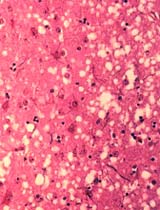

A toxoplasmose se manifesta freqüentemente no cérebro e nos olhos. O tratamento é à base de antibióticos como as sulfonamidas, pirimetamina e clindamicina.